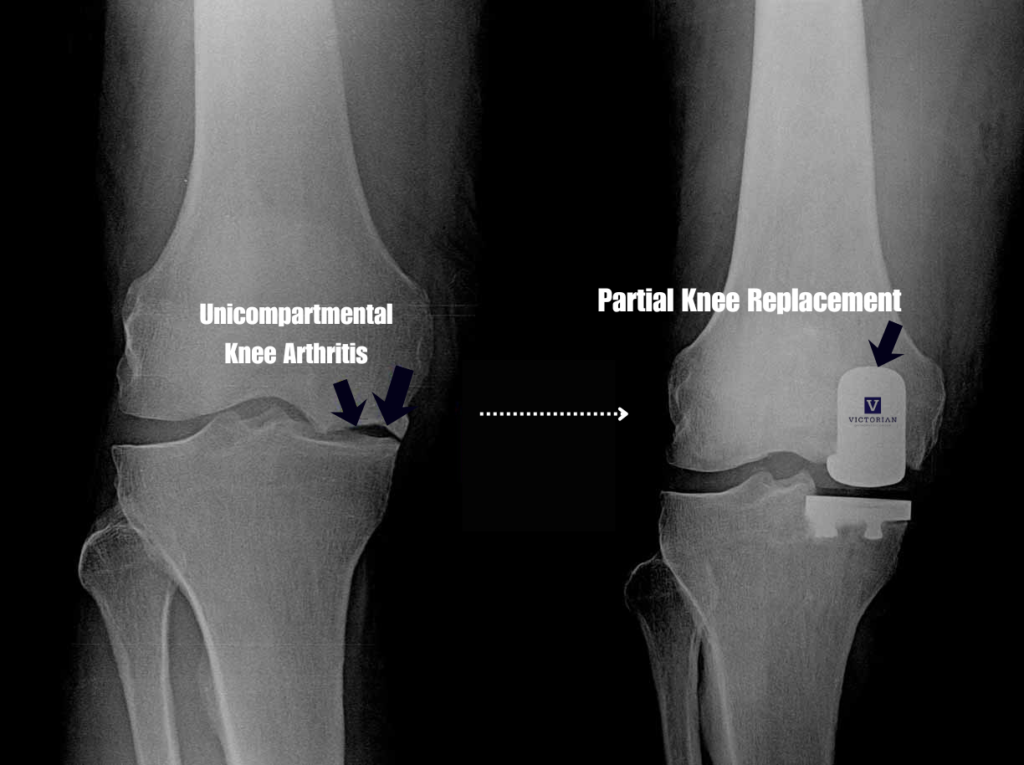

Unicompartmental (Partial) Knee Replacement Surgery